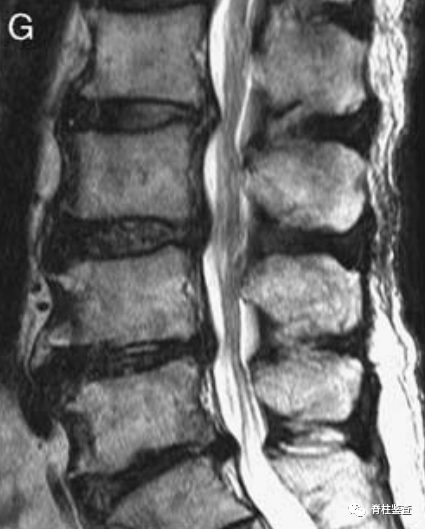

术后第1天显示,椎间盘充分移除;MR图像中的瘢痕组织限制了硬膜囊的充分扩张(白色↓)。